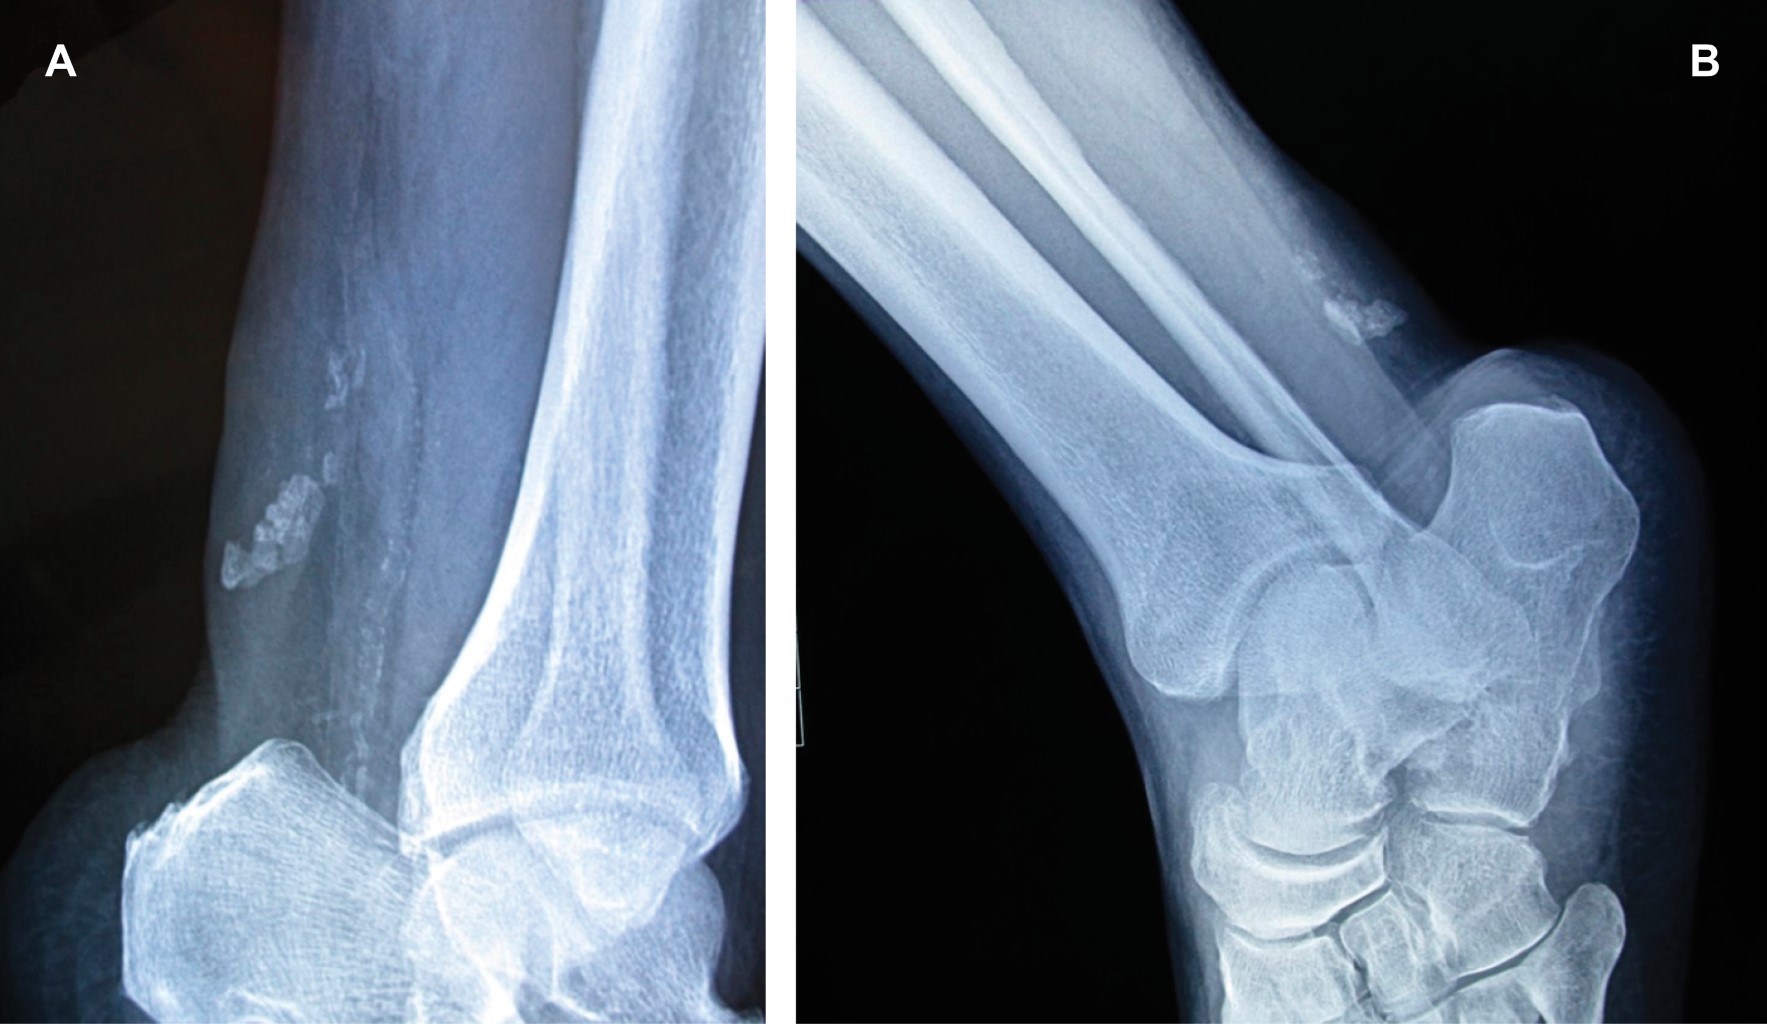

Achilles tendon xanthomas

Figure 1